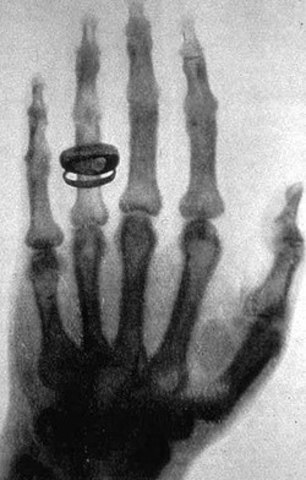

• Los rayos X son descubiertos

Los rayos X son descubiertos

El físico alemán Wilhelm Conrad Röntgen descubre los rayos X en 1895, mientras experimentaba con los tubos de Hittorff-Crookes y la bobina de Ruhmkorff para investigar la fluorescencia violeta que producían los rayos catódicos.